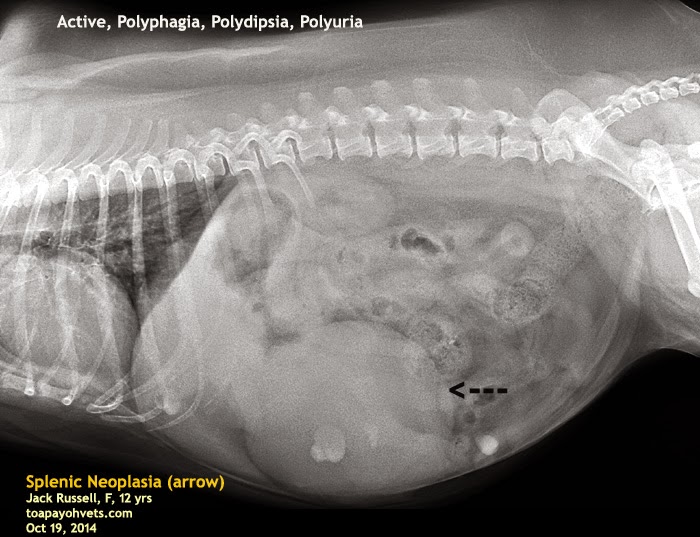

Liver Mass Dog X Ray. However, the microscopic spread of the tumor to other organs cannot be detected with these tests. although liver tumors cannot normally be diagnosed by clinical signs,. Ultrasound can determine if the tumor is massive, nodular, or diffuse, and whether it is in more. ultrasound is the most common diagnostic that is used to identify liver tumors. the most common primary liver tumor in dogs (second most common primary liver tumor in cats) is hepatocellular carcinoma (hcc). here’s what to know about the signs of liver cancer in dogs, diagnosis, and possible treatments, and the impact liver cancer may have on your dog’s lifespan. ultrasound is more sensitive for the detection of masses on the liver. dogs often have clinical signs that could be attributed to a liver mass.6 in some dogs, however, hepatic masses are found incidentally.16 historical findings can include anorexia, hyporexia, lethargy, weakness, vomiting, weight loss, diarrhea, polyuria, and polydipsia.1,6 clinical signs can include hepatomegaly, palpable abdominal mass.

ultrasound is the most common diagnostic that is used to identify liver tumors. However, the microscopic spread of the tumor to other organs cannot be detected with these tests. Ultrasound can determine if the tumor is massive, nodular, or diffuse, and whether it is in more. dogs often have clinical signs that could be attributed to a liver mass.6 in some dogs, however, hepatic masses are found incidentally.16 historical findings can include anorexia, hyporexia, lethargy, weakness, vomiting, weight loss, diarrhea, polyuria, and polydipsia.1,6 clinical signs can include hepatomegaly, palpable abdominal mass. although liver tumors cannot normally be diagnosed by clinical signs,. the most common primary liver tumor in dogs (second most common primary liver tumor in cats) is hepatocellular carcinoma (hcc). ultrasound is more sensitive for the detection of masses on the liver. here’s what to know about the signs of liver cancer in dogs, diagnosis, and possible treatments, and the impact liver cancer may have on your dog’s lifespan.